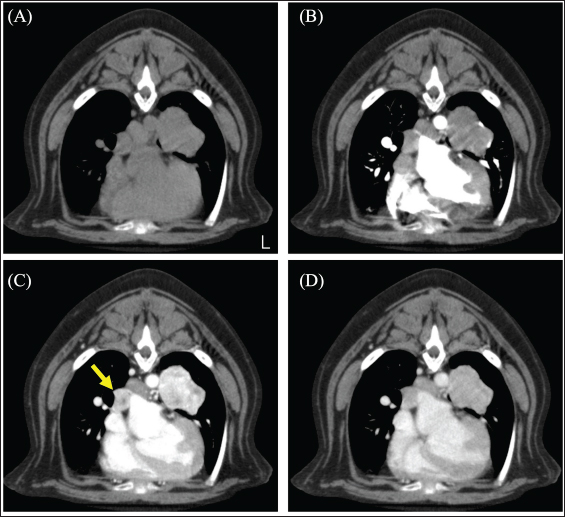

A 12-year-old spayed female French bulldog weighing 12.2 kg was visited by a veterinarian for a medical checkup. The dog had no clinical symptoms and was in good general condition; however, chest radiography revealed a mass in the left thoracic region. The dog was referred to the Okayama University of Science Veterinary Medical Teaching Hospital for close examination and treatments (day 1). The dog’s temperature was 38.3°C, heart rate was 100 beats/minute, and respiratory rate was 40 beats/minute. The non-obstructive blood pressure was as follows: systolic arterial blood pressure (SAP), 168 mmHg; mean arterial blood pressure (MAP), 124 mmHg; and diastolic arterial blood pressure (DAP), 119 mmHg. No abnormal values were observed in complete blood counts. Blood chemistry tests showed mild hypercholesterolemia (474 mg/dl), mild elevation of alkaline phosphatase (ALP; 629 U/l), and alanine aminotransferase (86 U/l) levels, and a mild decrease in blood urea nitrogen (7.5 mg/dl). The dog presented with polyurea or polydipsia. In the ACTH stimulation test, the postcortisol level was 27.8 µg/dl. Therefore, it was determined that the case presented with Cushing's syndrome as an underlying disease. Computed tomography (CT) scan (Aquilion Lightning; Canon Medical Systems Co., Otawara, Japan) performed in general anesthesia. Iopamidol (Oypalomin 300, Fuji Pharma, Japan) was used as a contrast medium [injection volume; 2.5 ml/kg (750 mgI/kg), injection time; 15 seconds]. Precontrast (before the injection of contrast medium), arterial phase (15 seconds after the start of injection), venous phase (40 seconds after the start of injection), the equilibrium phase (120 seconds after the start of injection) scans were obtained. The mass (42 × 39 × 44 mm) showed in the basilar left caudal lobe. The mass was in contact with the left cranial lobe, was strongly contrast-enhanced in the venous phase, and rapidly washed out in the equilibrium phase (Fig. 1). The right middle tracheobronchial lymph nodes were enlarged and showed a contrast-enhancement pattern similar to that of the mass in the left caudal lobe (Fig. 2). An incidentally enlarged right adrenal gland is also observed. The right adrenal gland was enlarged to 10 mm, spherical with a smooth limbus, contrast-enhanced at the limbus, peaked in the venous phase, and was attenuated in the equilibrium phase (Fig. 3). Based on the CT findings, we tentatively diagnosed the patient with a primary lung neuroendocrine tumor with lymph node metastasis. The anesthesia was stable during the CT scan, and no significant blood pressure fluctuations were observed.

Fig. 1. CT image of the chest. (A) Plain, (B) arterial phase, (C) venous phase, and (D) equilibrium phase. The mass was in contact with the left cranial lobe, was strongly contrast-enhanced in the venous phase, and rapidly washed out in the equilibrium phase.

Fig. 2. CT image of the chest. (A) Plain, (B) arterial phase, (C) venous phase, and (D) equilibrium phase. The yellow arrow indicates the right middle tracheobronchial lymph node. The lymph nodes were strongly contrast-enhanced in the venous phase and rapidly washed out in the equilibrium phase. The mean CT values of lung tumors were 72.01 HU in the arterial phase, 206.57 HU in the venous phase, and 132.17 HU in the equilibrium phase.

In this case, CT showed a left caudal lobar mass, enlarged middle tracheobronchial lymph nodes, and a right adrenal mass. The pulmonary mass was strongly enhanced in the venous phase and was washed out in the equilibrium phase. A previous study reporting the CT findings of paragangliomas in 10 dogs showed strong contrast enhancement in the arterial and venous phases (Gombert et al., 2022). The strong contrast-enhancing effect and subsequent washout of the left caudal lobar mass seen in this case are characteristic imaging findings that are suspicious for neuroendocrine tumors and are also seen in insulinomas and carcinoids, in addition to paragangliomas (Fukushima et al., 2016; Kutara et al., 2017). The resected lung mass was diagnosed as a neuroendocrine carcinoma by pathological examination, which was consistent with the imaging findings. In short, even in paragangliomas of the lung, this characteristic contrasting finding may help in decision-making. The enlarged right tracheobronchial lymph node showed the same contrast pattern as the mass and was suspected to be metastatic. Although pathological evaluation of the right adrenal mass was not performed in this case because it was not removed, it has been reported that adrenal masses can be diagnosed preoperatively using a triple-phase helical CT scan (Yoshida et al., 2016). In this case, the right adrenal mass was 10 mm in size with a smooth limbus and contrast enhancement at the limbus, peaking in the venous phase and diminishing in the equilibrium phase. Following previous reports, the right adrenal mass was considered an adrenal adenoma rather than a suspected pheochromocytoma. In this case, blood tests revealed elevated ALP levels, possibly due to the corticosteroids. Thus, based on these results, it was unlikely that the left lung mass was a metastatic lesion of the right adrenal mass and was considered a primary lung mass.